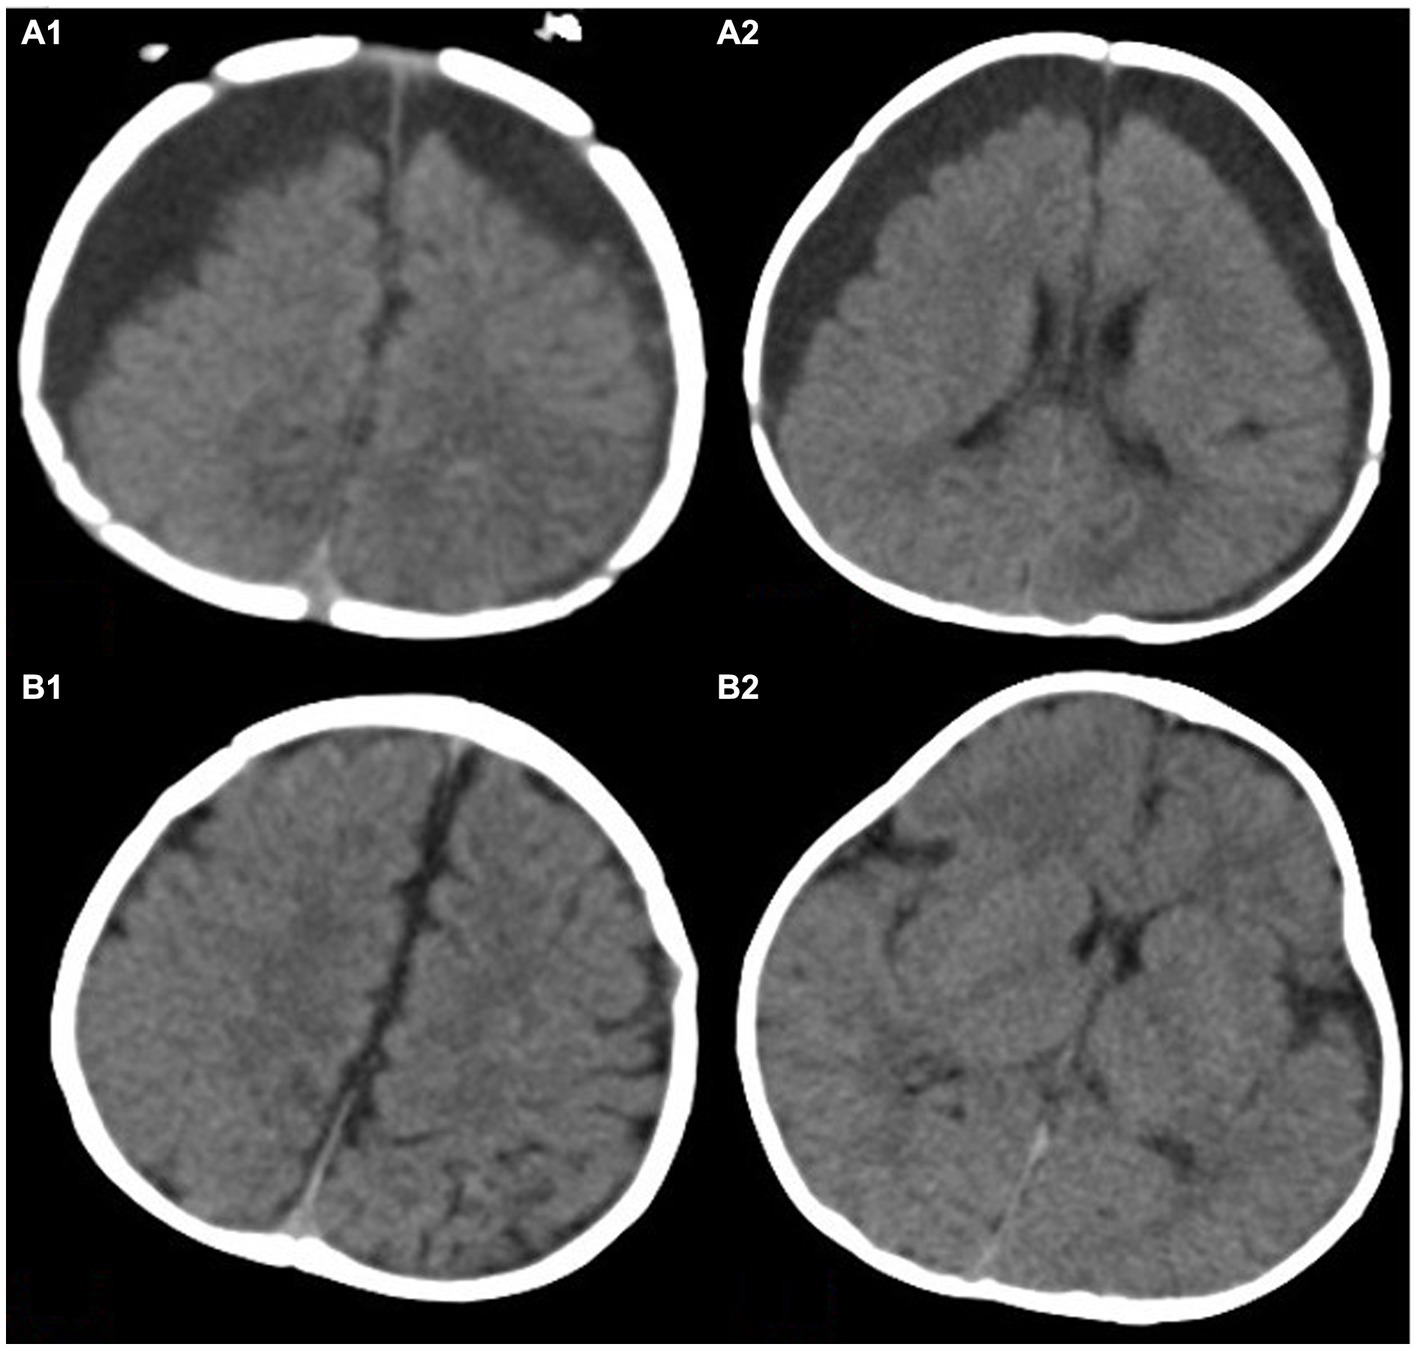

Figure 2

This image shows a 4-month-old child with subdural effusion in bilateral frontotemporal parietal lobe in (A1,A2), with a subdural residual cavity thickness greater than 1.5 cm. Brain tissue atrophy is also visible. Panels (B1,B2) show the extent of brain re-expansion after 6 months of hyperbaric oxygen therapy. The bilateral subdural residual cavities have significantly improved.